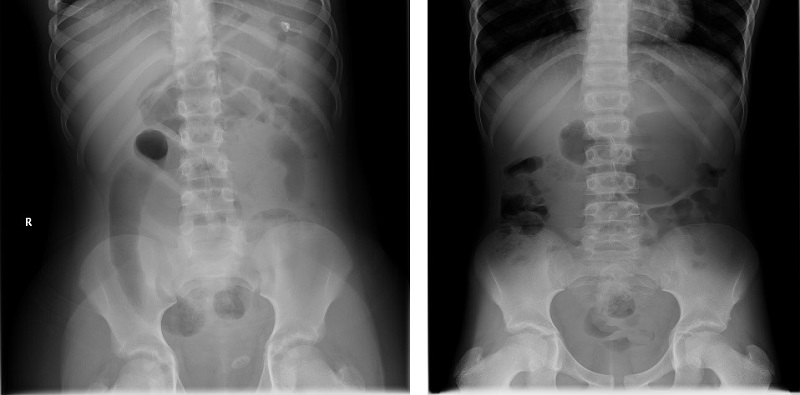

En cuanto a las pruebas de imagen, en el 50% se realizó radiografía simple de abdomen como prueba inicial; dichos pacientes fueron los dos con antecedentes quirúrgicos. En ambos se objetivó obstrucción intestinal a distintos niveles (Fig. 1). La ecografía abdominal se realizó en tres de los pacientes; en uno de ellos se desestimó por el mal estado general. En la ecografía se observó el signo del remolino sugestivo de vólvulo en uno de ellos, y en los otros dos, signos indirectos de sufrimiento de asas y líquido libre sin objetivarse una etiología clara. Además, en dos de los pacientes se realizó tomografía computarizada (TC) abdominal, constatándose la obstrucción intestinal en asa cerrada y signos de isquemia intestinal en ambas exploraciones. Uno de ellos asoció signo del remolino positivo.

| Figura 1. Radiografía abdominal (caso 1 y 2): signos de obstrucción intestinal a distintos niveles. Patrón de aireación anómalo, sugestivo de obstrucción intestinal |

Ante la sospecha de un vólvulo intestinal, la primera prueba complementaria a realizar sería la radiografía de abdomen, en especial en los pacientes con antecedentes quirúrgicos6,7. Los hallazgos pueden resultar inespecíficos y principalmente observaremos signos de obstrucción intestinal como el signo de la doble burbuja, malposición intestinal y, en casos de perforación, se podrá observar neumatosis intestinal con neumoperitoneo. La ecografía abdominal es la segunda prueba diagnóstica a realizar y, aunque es menos sensible que la radiografía, es más específica. En ella se puede observar el “signo del remolino”, donde se visualiza la arteria mesentérica superior con un remolino de asas intestinales a su alrededor, hallazgo que es patognomónico de vólvulo intestinal. Hay que tener en cuenta que la normalidad de estas dos pruebas radiológicas no descarta la presencia de vólvulo8,9.